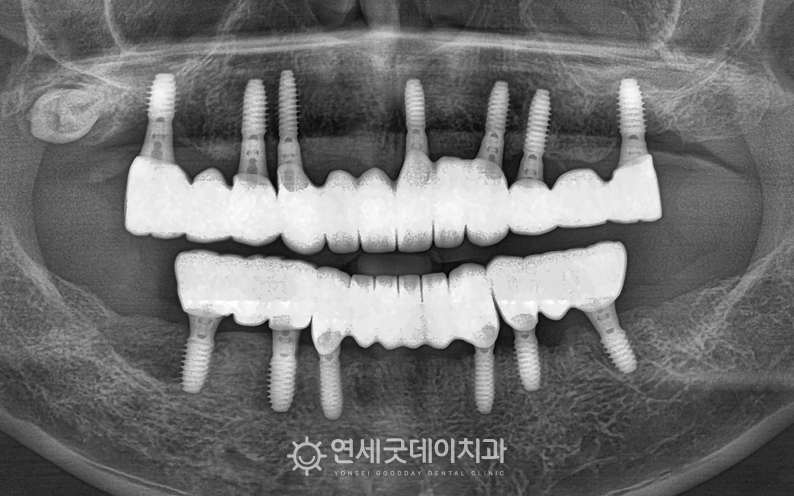

전악임플란트 치료를 마친 후의 모습입니다. 광범위하게 소실되었던 잇몸뼈는 뼈이식을 통해

특히 길어보였던 전치부 잇몸 라인을 보완하며 또한 어금니 교합도 안정적으로 형성되었으며

치료 전 모습이 떠오르지 않을 정도로